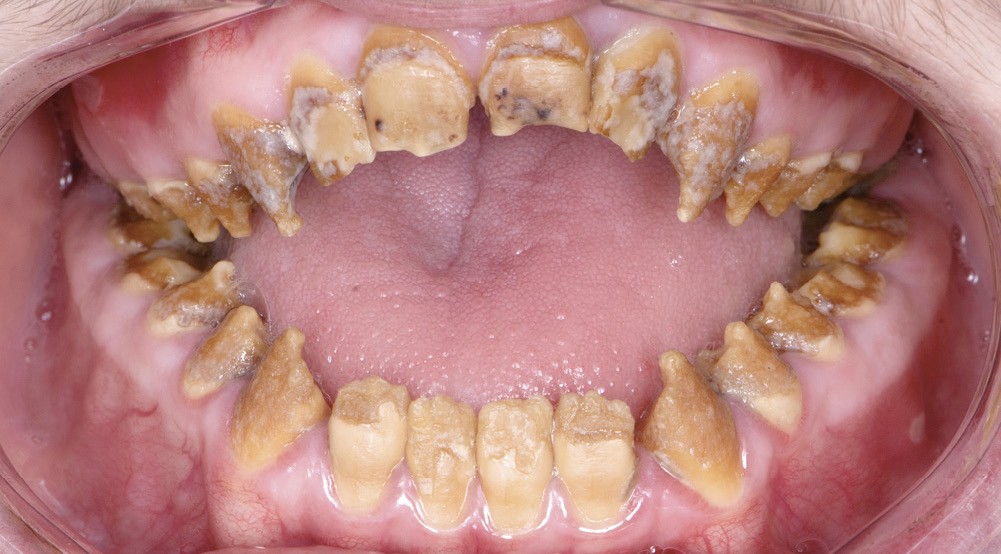

Dans tous les cas, le préjudice de l’enfant ou de l’adulte est non seulement fonctionnel – caractérisé par des sensibilités dentaires plus ou moins accrues, des malpositions occlusales associées parfois à une perte de dimension verticale – mais aussi esthétique, par l’aspect plus ou moins coloré et malformé des dents (fig. 1a, b). Le retentissement psychologique est variable selon la sévérité de l’atteinte et l’environnement social, mais reste important, surtout dans l’enfance [3].